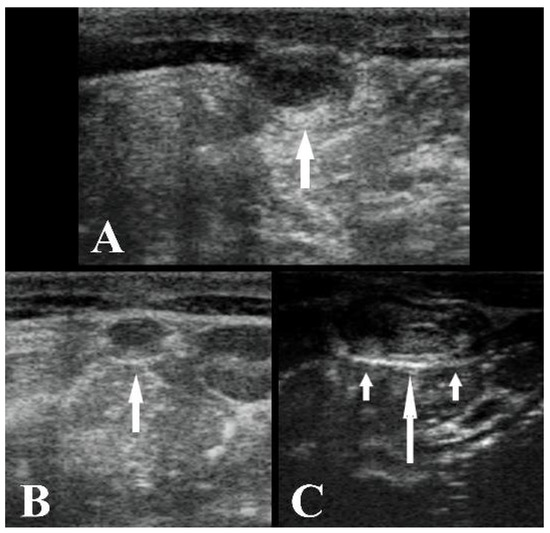

2.2. Ultrasonography Technique